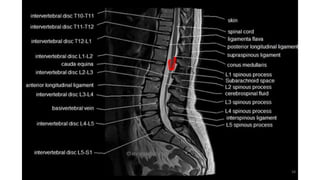

MRI spine and sequences

Spine sequences

• T1

• T2

• STIR

• T1C

• DIXON

• DWI

• SWI